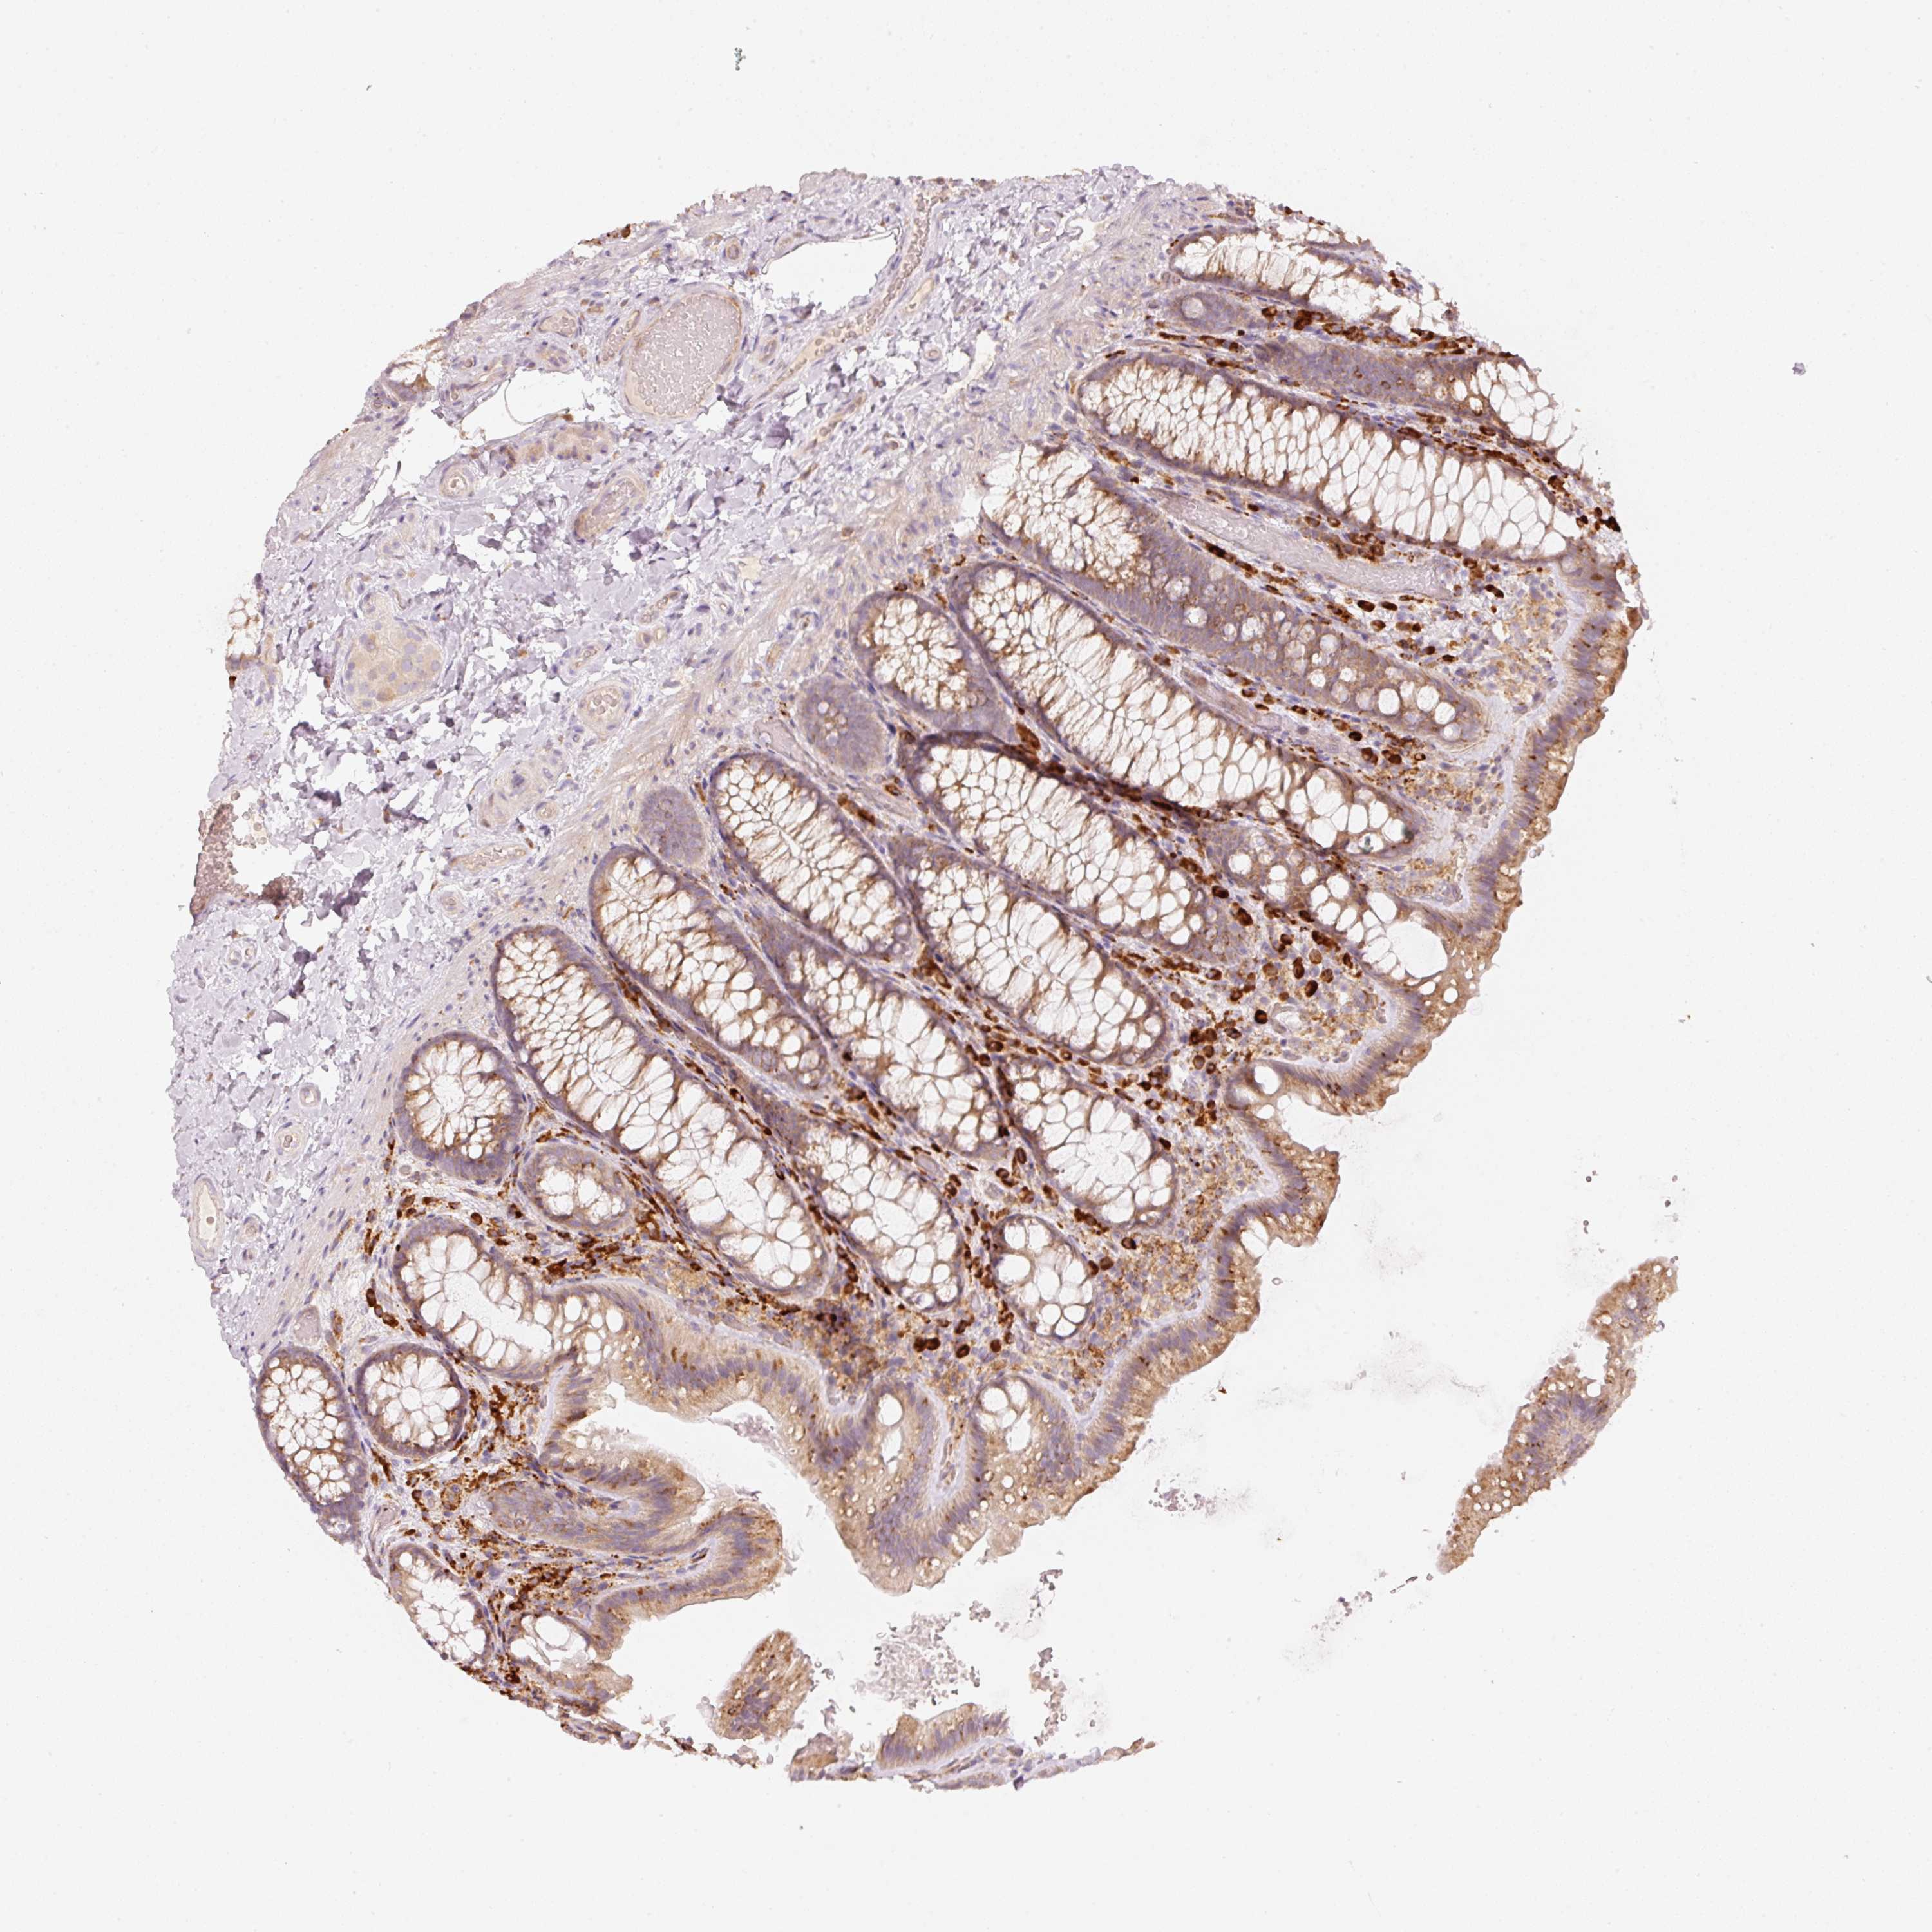

OR13C3